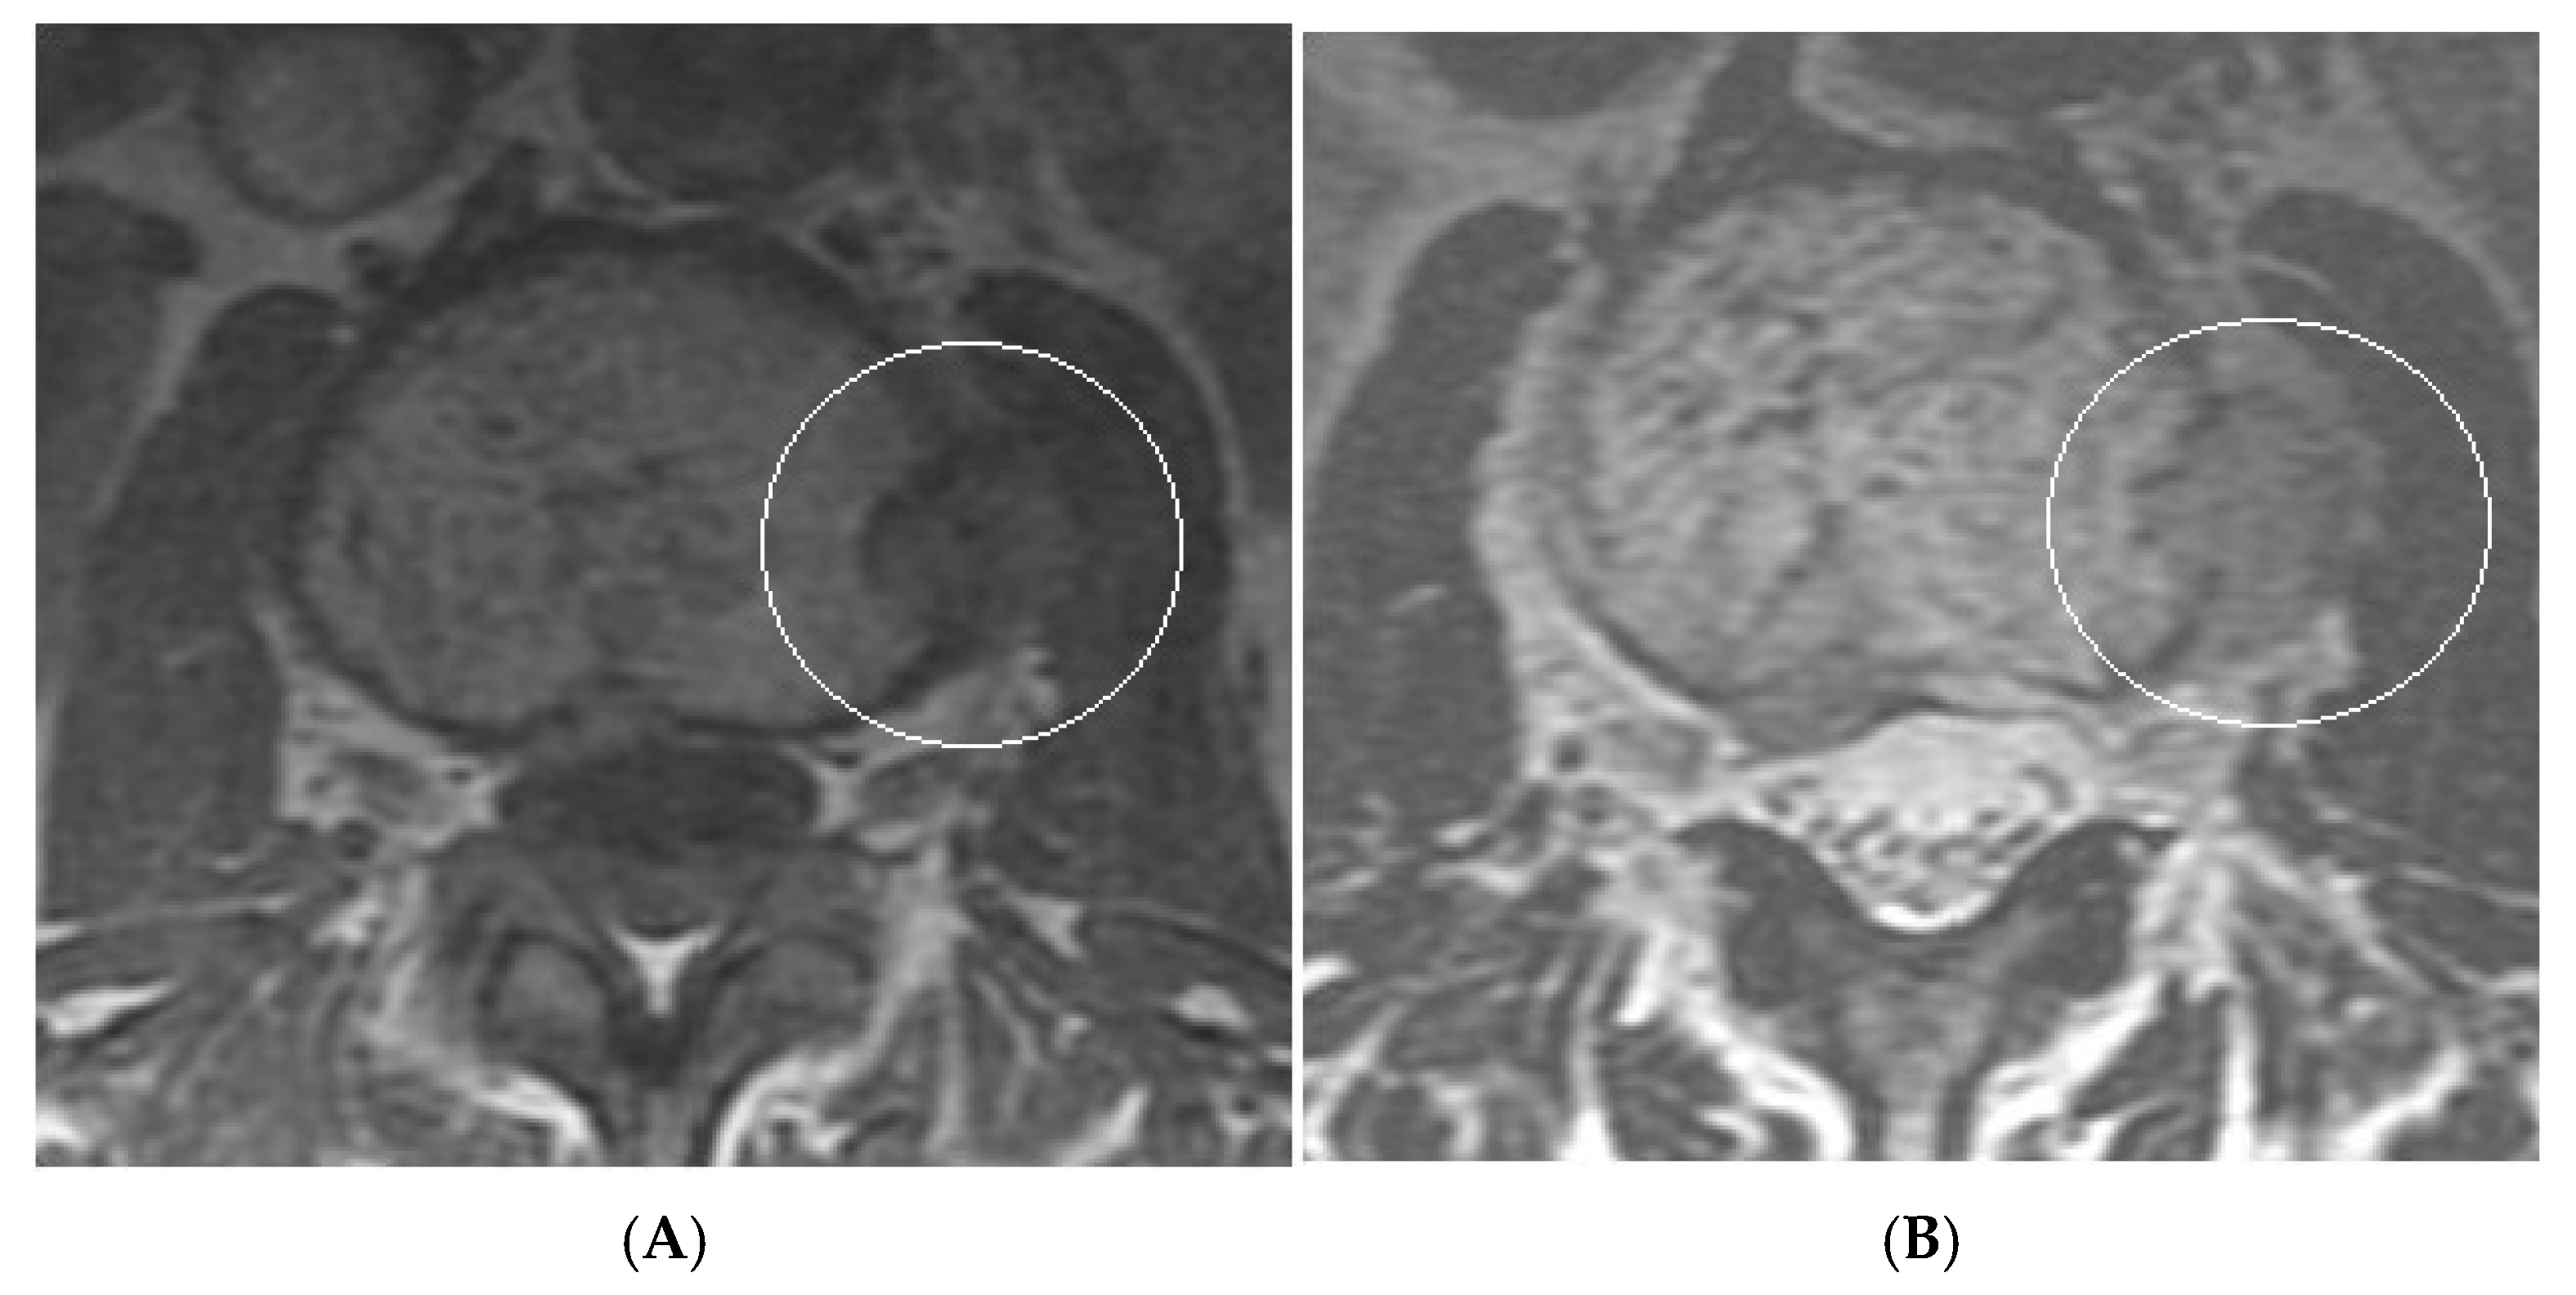

Figure 15.

Collision Lesions: Renal cell carcinoma metastases within a haemangioma of vertebral body, Case 1. (A) Axial T1W MRI—A large T1 hyperintense lesion with typical appearances of a haemangioma within the vertebral body, associated with a smaller peripheral located T1 isointense lesion with extraosseous component (circled). (B) Axial T2W MRI—Same case with T2 hyperintense vertebral body lesion confirming internal fat content and the eccentrically located T2 hyper- to isointense lesion proven to be a renal cell carcinoma on histology.